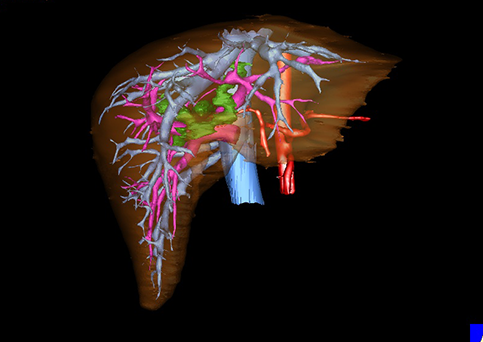

图12:先天性胆管扩张症梭状型合并左右肝管分别汇入胆总管囊肿三维重建虚拟肝脏、胆道显像

a 图为术前二维CT图像;b 图为CT经多平面重组技术(MPR)所得的三维重建图像,可粗略地判断病变胆管的位置;c 图为MRCP显示胆总管梭状扩张;d 图为术前Hisense CAS三维重建显示胆管的分布走形及其与肝内三套血管系统的解剖关系;e 图为胆道系统立体形态及与肝脏整体的空间关系,箭头处显示对于左右肝管分别汇入胆总管囊肿中,整个肝总管也明显扩张而成为囊肿的一部分。术前规划为先将囊肿完全切除,左右肝管合并成形后再与空肠吻合。